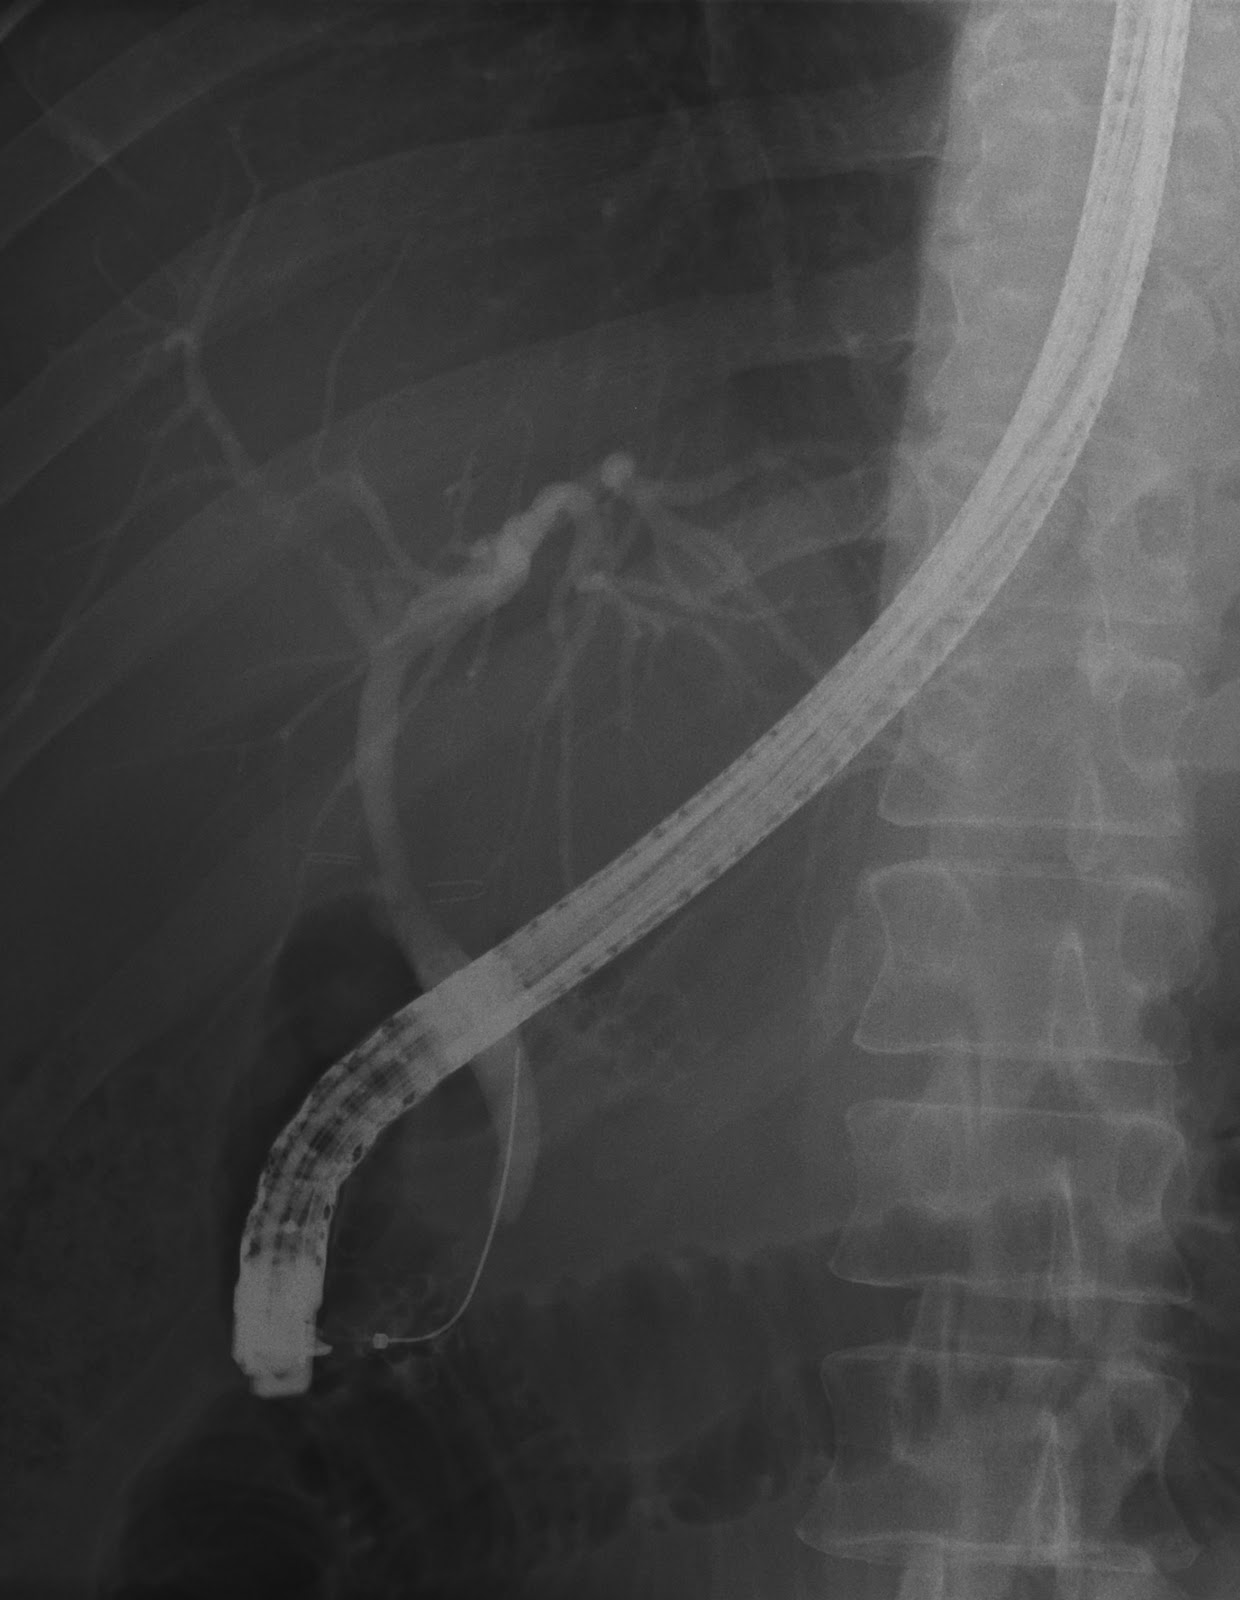

XRay Vision A Radiography Blog ERCP Anatomy, Procedure and the Ercp Xray Labeled The normal cbd diameter of ercp imaging will be greater than that of ultrasound, ct, and mri, most likely related to the combination of active injection of contrast material. Despite the near ubiquitous access to advanced radiology and endoscopic ultrasound (eus) in north america, ercp still has. Ercp is a type of endoscopic procedure used to examine and treat the. Ercp Xray Labeled.

ERCP; 내시경적역행성담췌관조영술, 담석제거, ERBD, ENBD 네이버 블로그 Ercp Xray Labeled Ercp is a type of endoscopic procedure used to examine and treat the biliary tree (the gallbladder, bile and pancreatic ducts). Ercp (endoscopic retrograde cholangiopancreatography) is a specialized technique used to study the pancreas,. Despite the near ubiquitous access to advanced radiology and endoscopic ultrasound (eus) in north america, ercp still has. The normal cbd diameter of ercp imaging will. Ercp Xray Labeled.